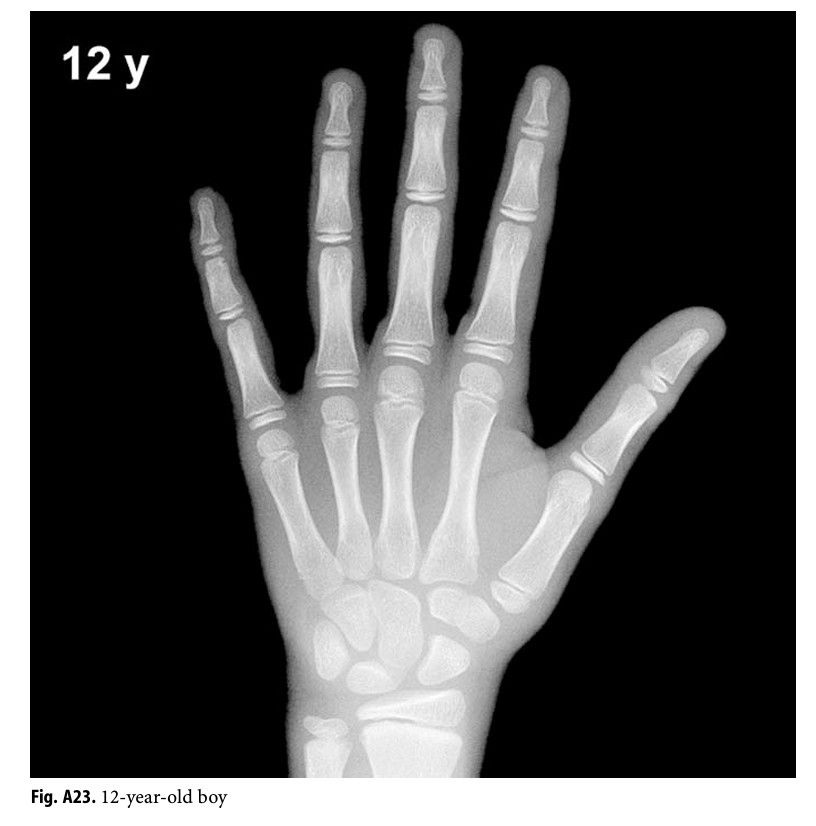

骨齡是透過手部 X 光,觀察骨頭的成熟程度與生長板的空間,

幫助醫師了解孩子目前的生長發育階段。

它可以告訴我們四件事:

- 骨骼成熟速度是否正常

- 是否有提早或延後發育的情況

- 剩餘的成長空間大約還有多少

- 輔助預估孩子的成人身高

骨齡不只是一張 X 光,它是幫家長和醫師一起做決策的工具。

Gilsanz, Vicente, and Osman Ratib. Hand Bone Age: A Digital Atlas of Skeletal Maturity. Springer, 2005.